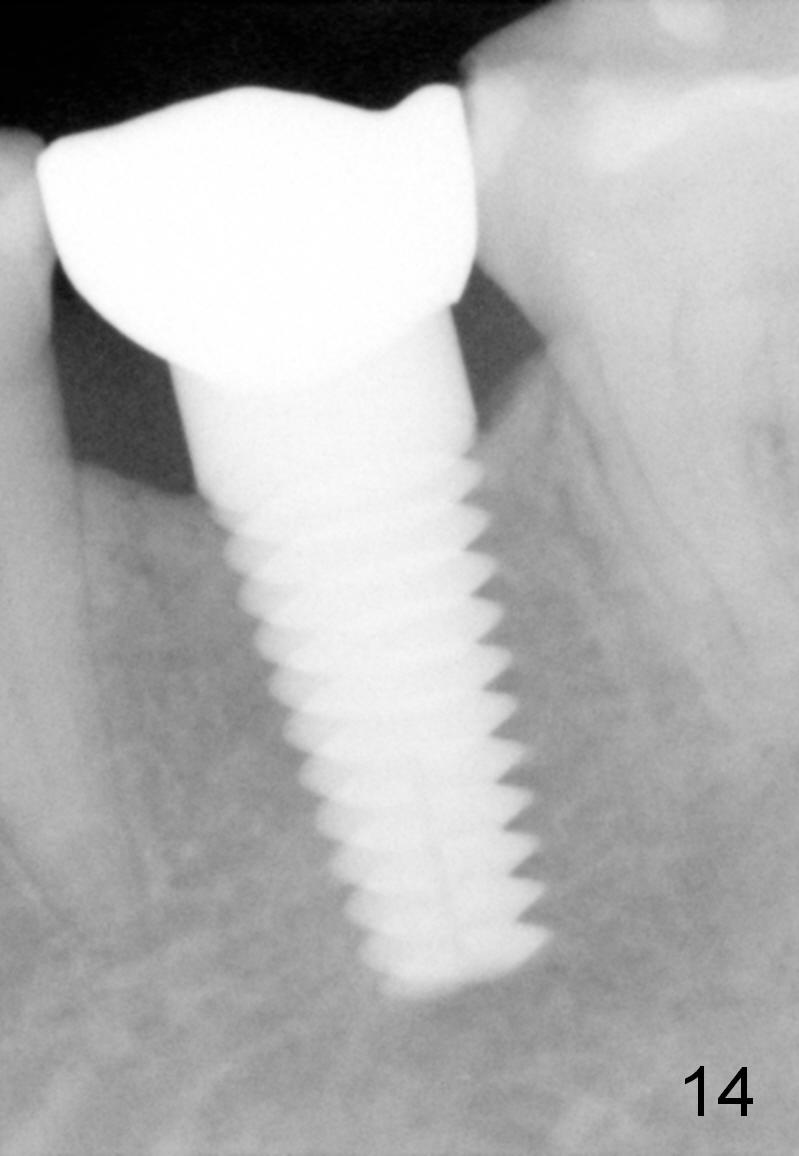

Eleven months post bonding (17 months postop), there is cortical bone formation at the mesial and distal crests (Fig.14). It remains the same 1 year 10 months post bonding (Fig.15). There is no bone loss 3 years 5 months post cementation (Fig.16). In fact the crestal cortical bone thickens.